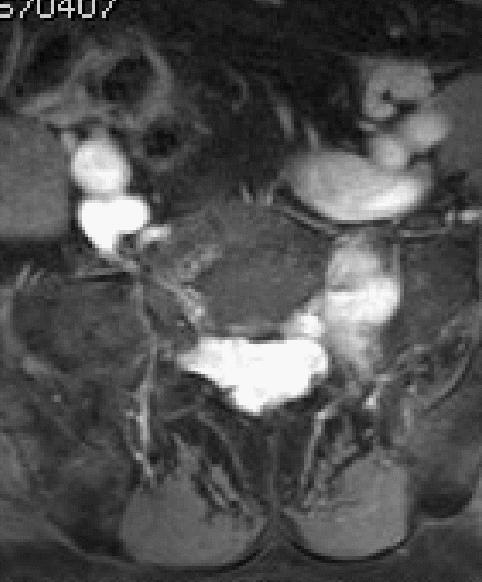

MRI增强

如图所示,分别为T1WI增强矢状位、冠状位、轴位,T1WI增强矢状位与T2WI压脂像非常相像,注意椎管内脑脊液信号,T1WI增强为低信号与T2WI压脂像高信号正好相反。红色箭头所示病灶明显强化,呈亮灯征感觉,清晰显示病灶范围,绿色箭头所示为病灶侵及骶1椎体后缘形成不规则形骨质破坏区。